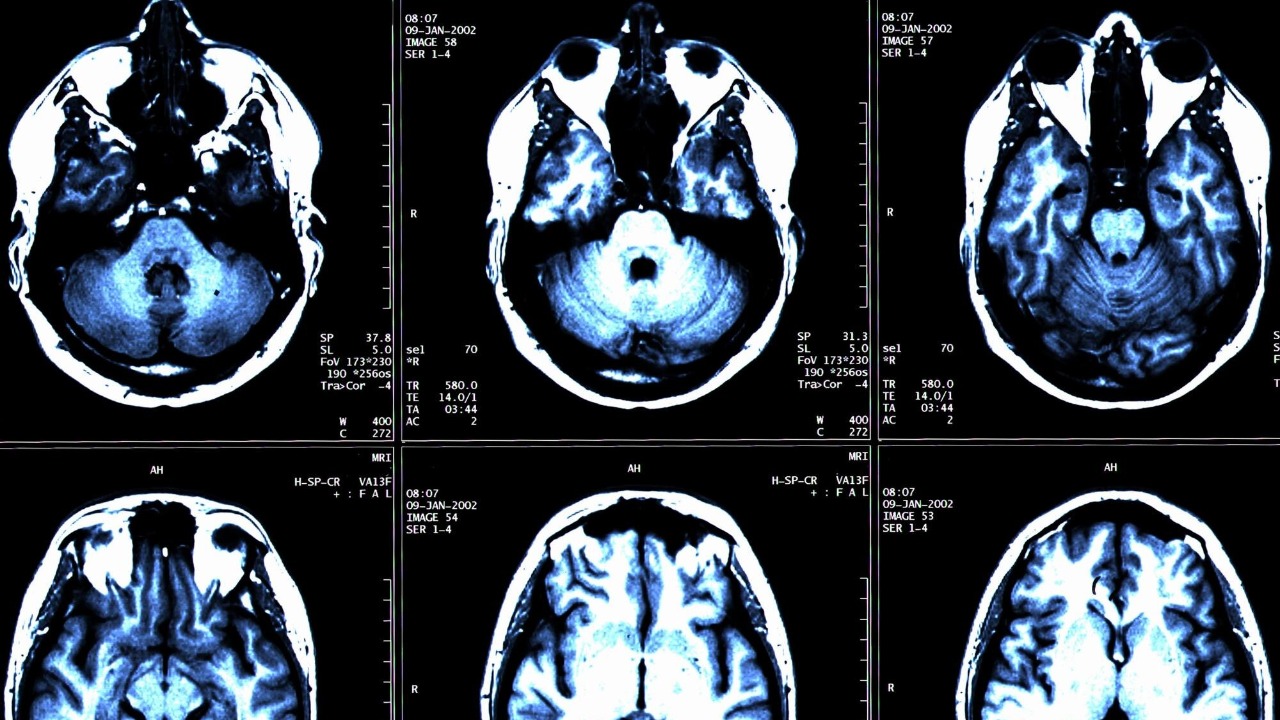

Astronauts’ brains warp in shape after spaceflight, study reveals

Read More: Astronauts’ brains warp in shape after spaceflight, study revealsHuman brains evolved under the steady pull of gravity, yet modern astronauts are spending months at a time in orbit,…